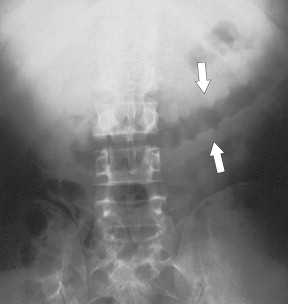

Plain radiography may demonstrate an ileus, sometimes confined to the left colon. As the disease progresses, bowel wall thickening develops ( Fig. 5-34 ) with a toxic megacolon if severe ( Fig. 5-35 ). BE is now rarely performed, but results demonstrate thickened folds and ulceration, either linear or with mucosal sloughing. Healing can lead to stricture formation ( Fig. 5-36 ). The findings are now usually made by CT and are similar to other forms of colitis (inflammatory bowel disease, infectious colitides, and radiation colitis if the radiation field included the colon). The disease is suggested in the appropriate clinical setting and by the left-sided distribution of the colonic changes ( Fig. 5-37 ). Severely affected patients show colonic pneumatosis as the gas permeates the damaged mucosa, which can then enter the mesenteric venous system and be recognized as mesenteric venous gas (particularly at CT) and ultimately intrahepatic portal venous gas. Occasionally, ischemia occurs proximal to an obstructing colonic stricture, such as colonic adenocarcinoma. The obstruction causes marked distention of the proximal colon, compromising its vascular supply or directly invading mesenteric vasculature ( Fig. 5-38 ).

Figure 5-36, BE in a 71-year-old man with a left mid-descending colon stricture ( arrow ) secondary to fibrosis from prior ischemic colitis.